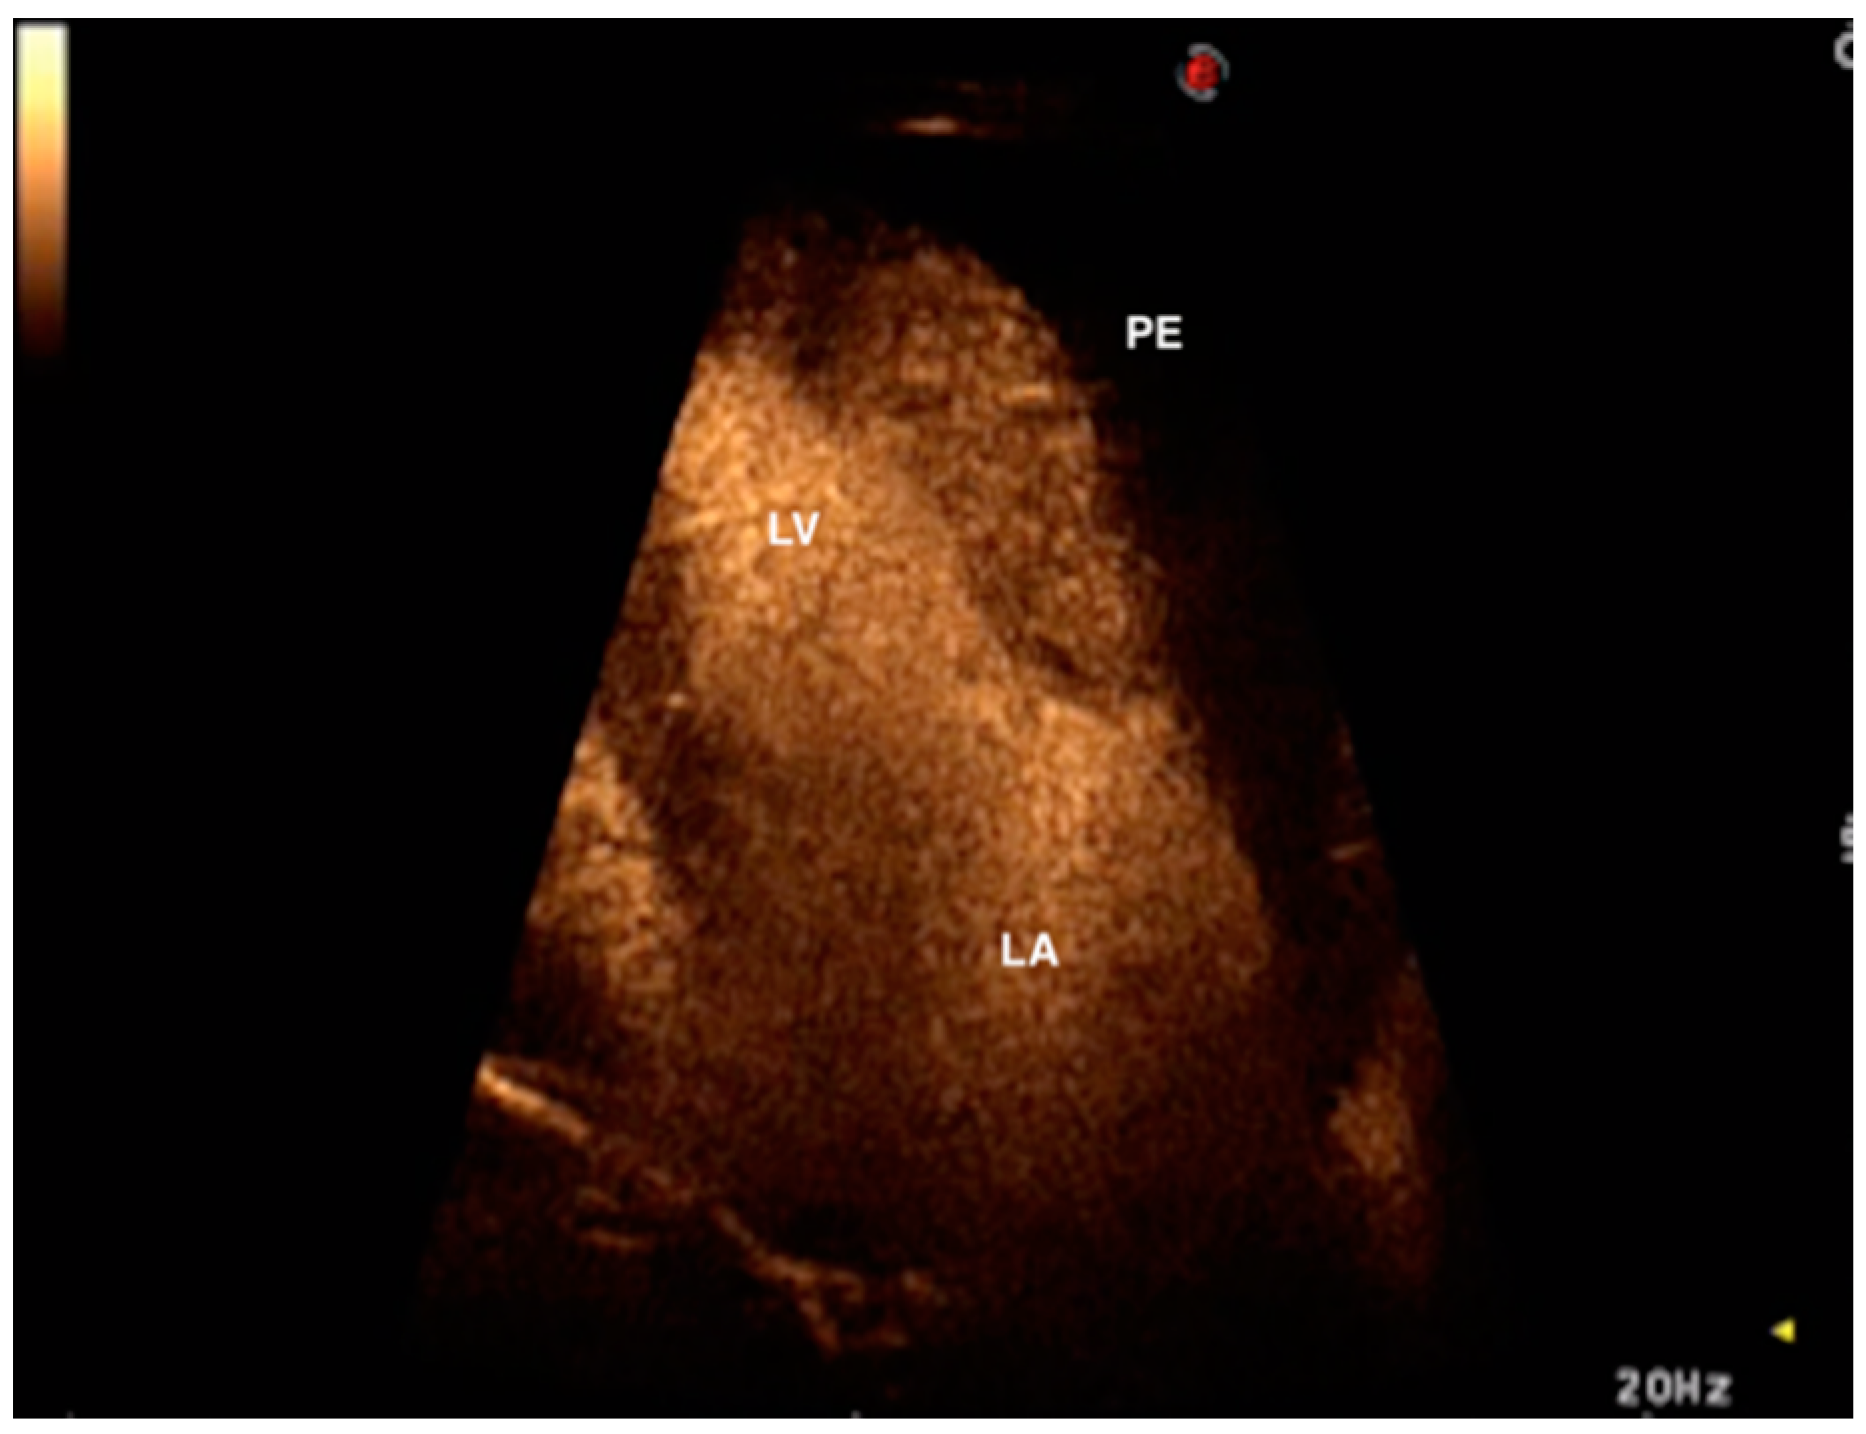

Left Atrial Mural Thrombosis and Hemopericardium in a Dog with Myxomatous Mitral Valve Disease

2. Case Presentation